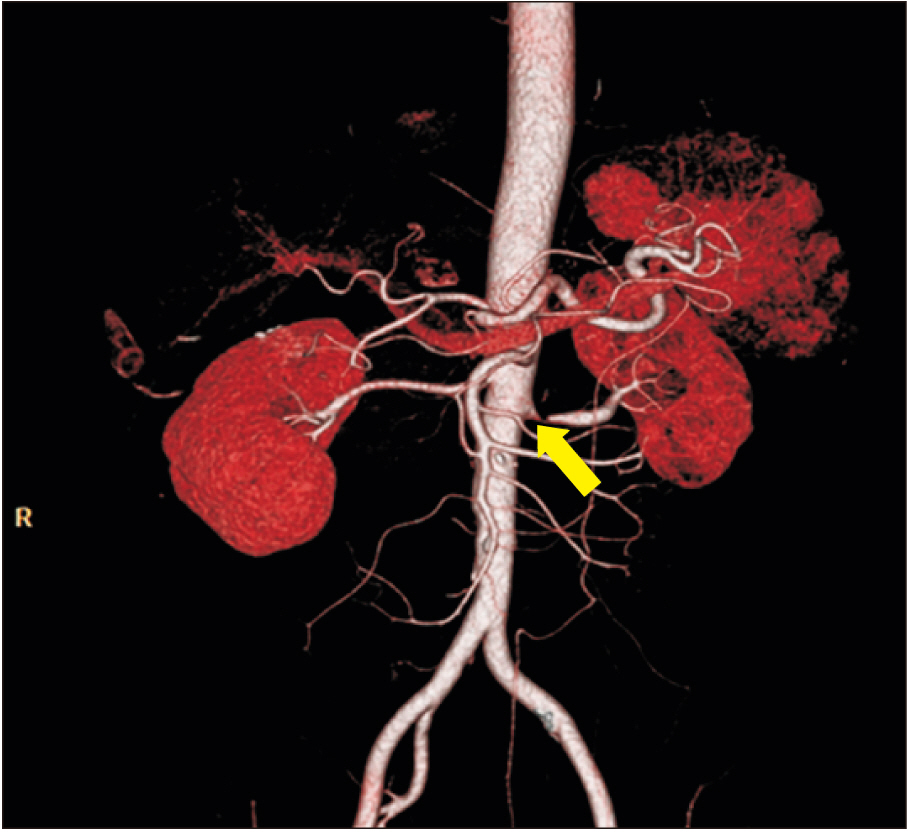

- Flank pain is a common reason for visits to the emergency room. The most common reason warranting hospital visits are urology-related problems. However, there are many other causes, such as musculoskeletal lesions, that difficult to achieve a correct diagnosis. Here, we describe a rare case of flank pain caused by thoracolumbar junction syndrome, accompanying renal artery stenosis. A 54-year-old male with hypertension presented with severe left flank pain for 1 week. Initially, he was diagnosed with left renal artery stenosis by computed tomography and decreased renal function on renal scan (Tc-99m DTPA). Although a stent was inserted into the left renal artery, flank pain persisted with only minor improvement. Through detailed physical examination, he was finally diagnosed with thoracolumbar junction syndrome. After three injections in the left deep paravertebral muscles at the T10–T12 levels, flank pain completely ceased. Clinicians must consider thoracolumbar junction syndrome, when treating patients with flank pain.

Figure